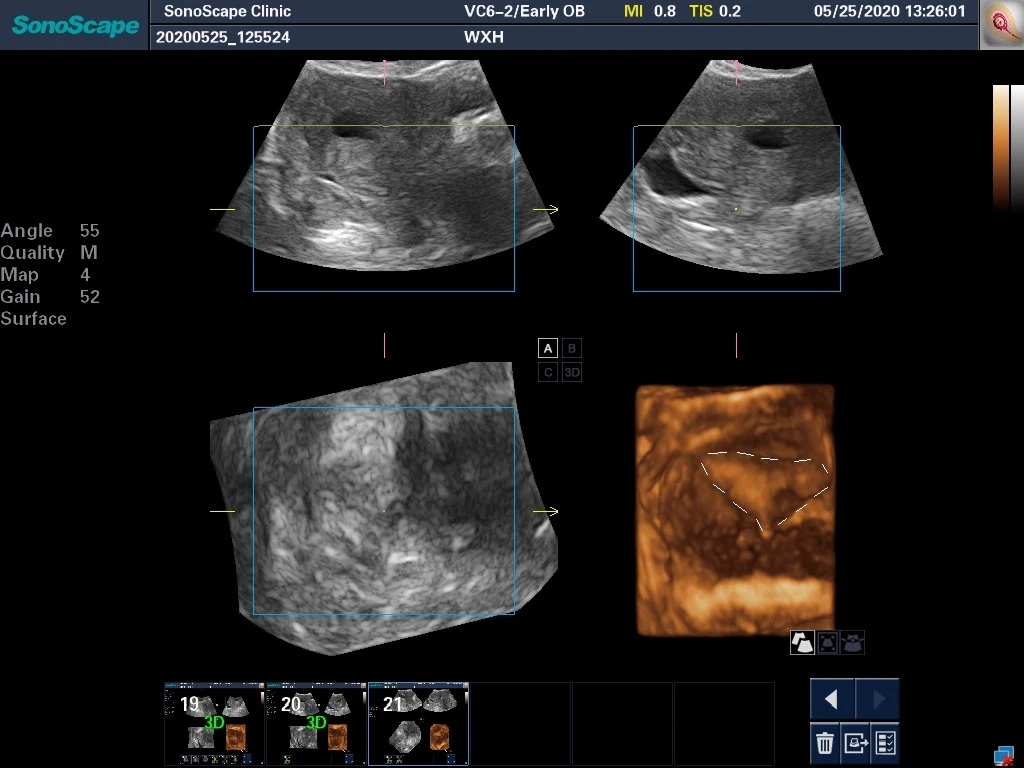

这台彩超还允许我们在手术中直接进行3D重建成像。

上图白线所标记部位就是恢复后的整体子宫腔,与正常的宫腔相比已经无明显差异。